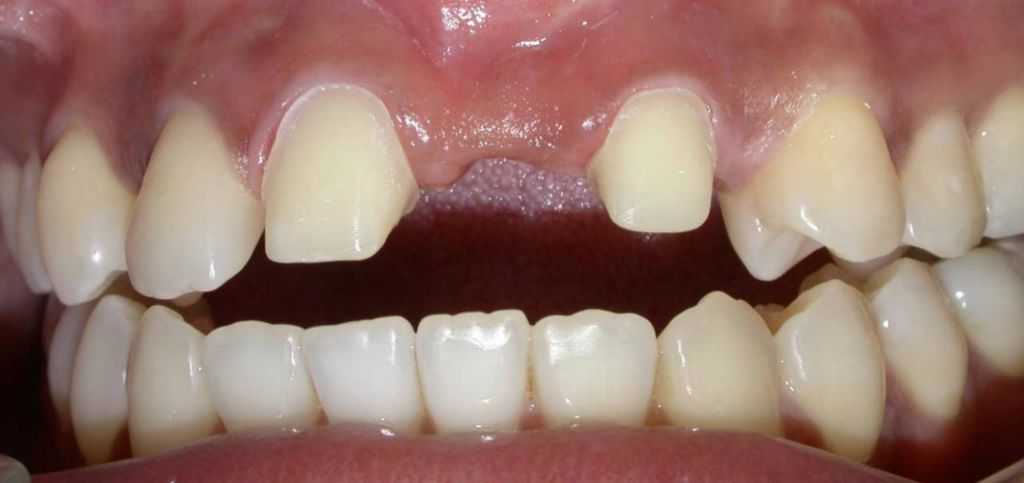

Before

-

After